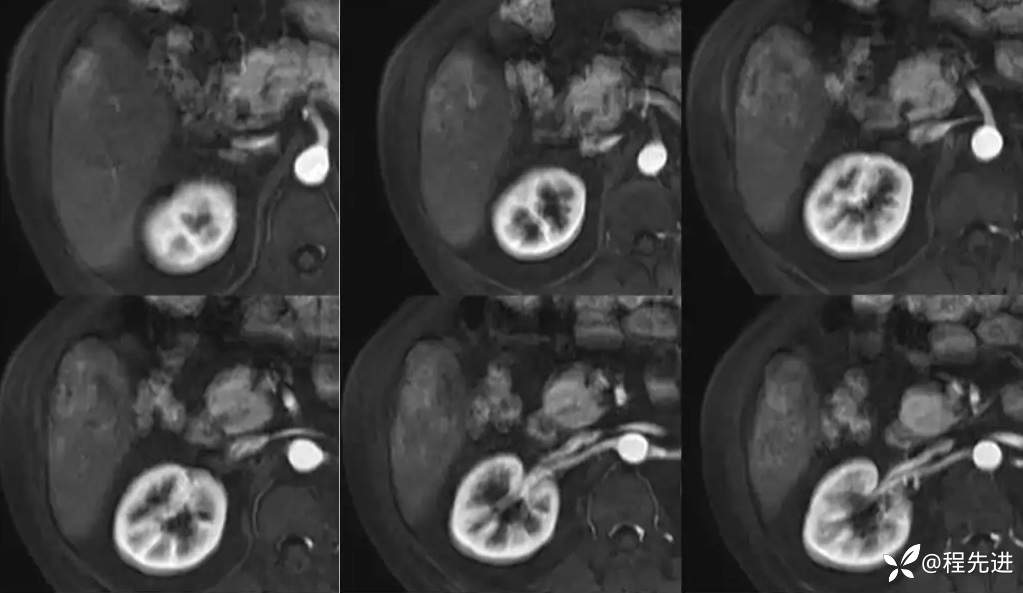

CT平扫:

动脉期:

门静脉期:

门静脉期冠状位:

延迟期: